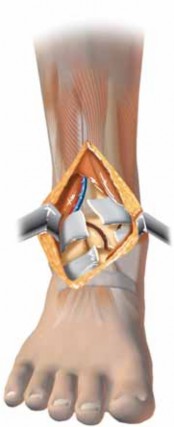

39.

---

Anterior tibial artery and vein Extensor hallucis longus Extensor digitorum communis Anterolateral approach Deep peroneal n. Tibialis anterior tendon Anteromedial approach Tibia Fibula Peroneus longus m. Peroneus brevis m. Posterolateral approach Sural n. Sural v. Saphenous v. Posteromedial approach Posterior tibial artery and vein Tibial n. Flexor hallucis longus m. Achilles tendon ### FIG 6 • Approaches to the tibial plafond are probably best tailored to match the injury pattern. More than 90% of plafond fractures are well approached anteriorly (anteromedially or anterolaterally), but other approaches are sometimes useful.